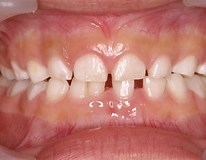

まずは癒合歯です。これは出現頻度も高くご存知の方も

いらっしゃると思います。

乳前歯部で多く、2本の歯がくっついて1本になっているので癒合部の溝に

プラークが溜まりやすく、虫歯になりやすいところになります。